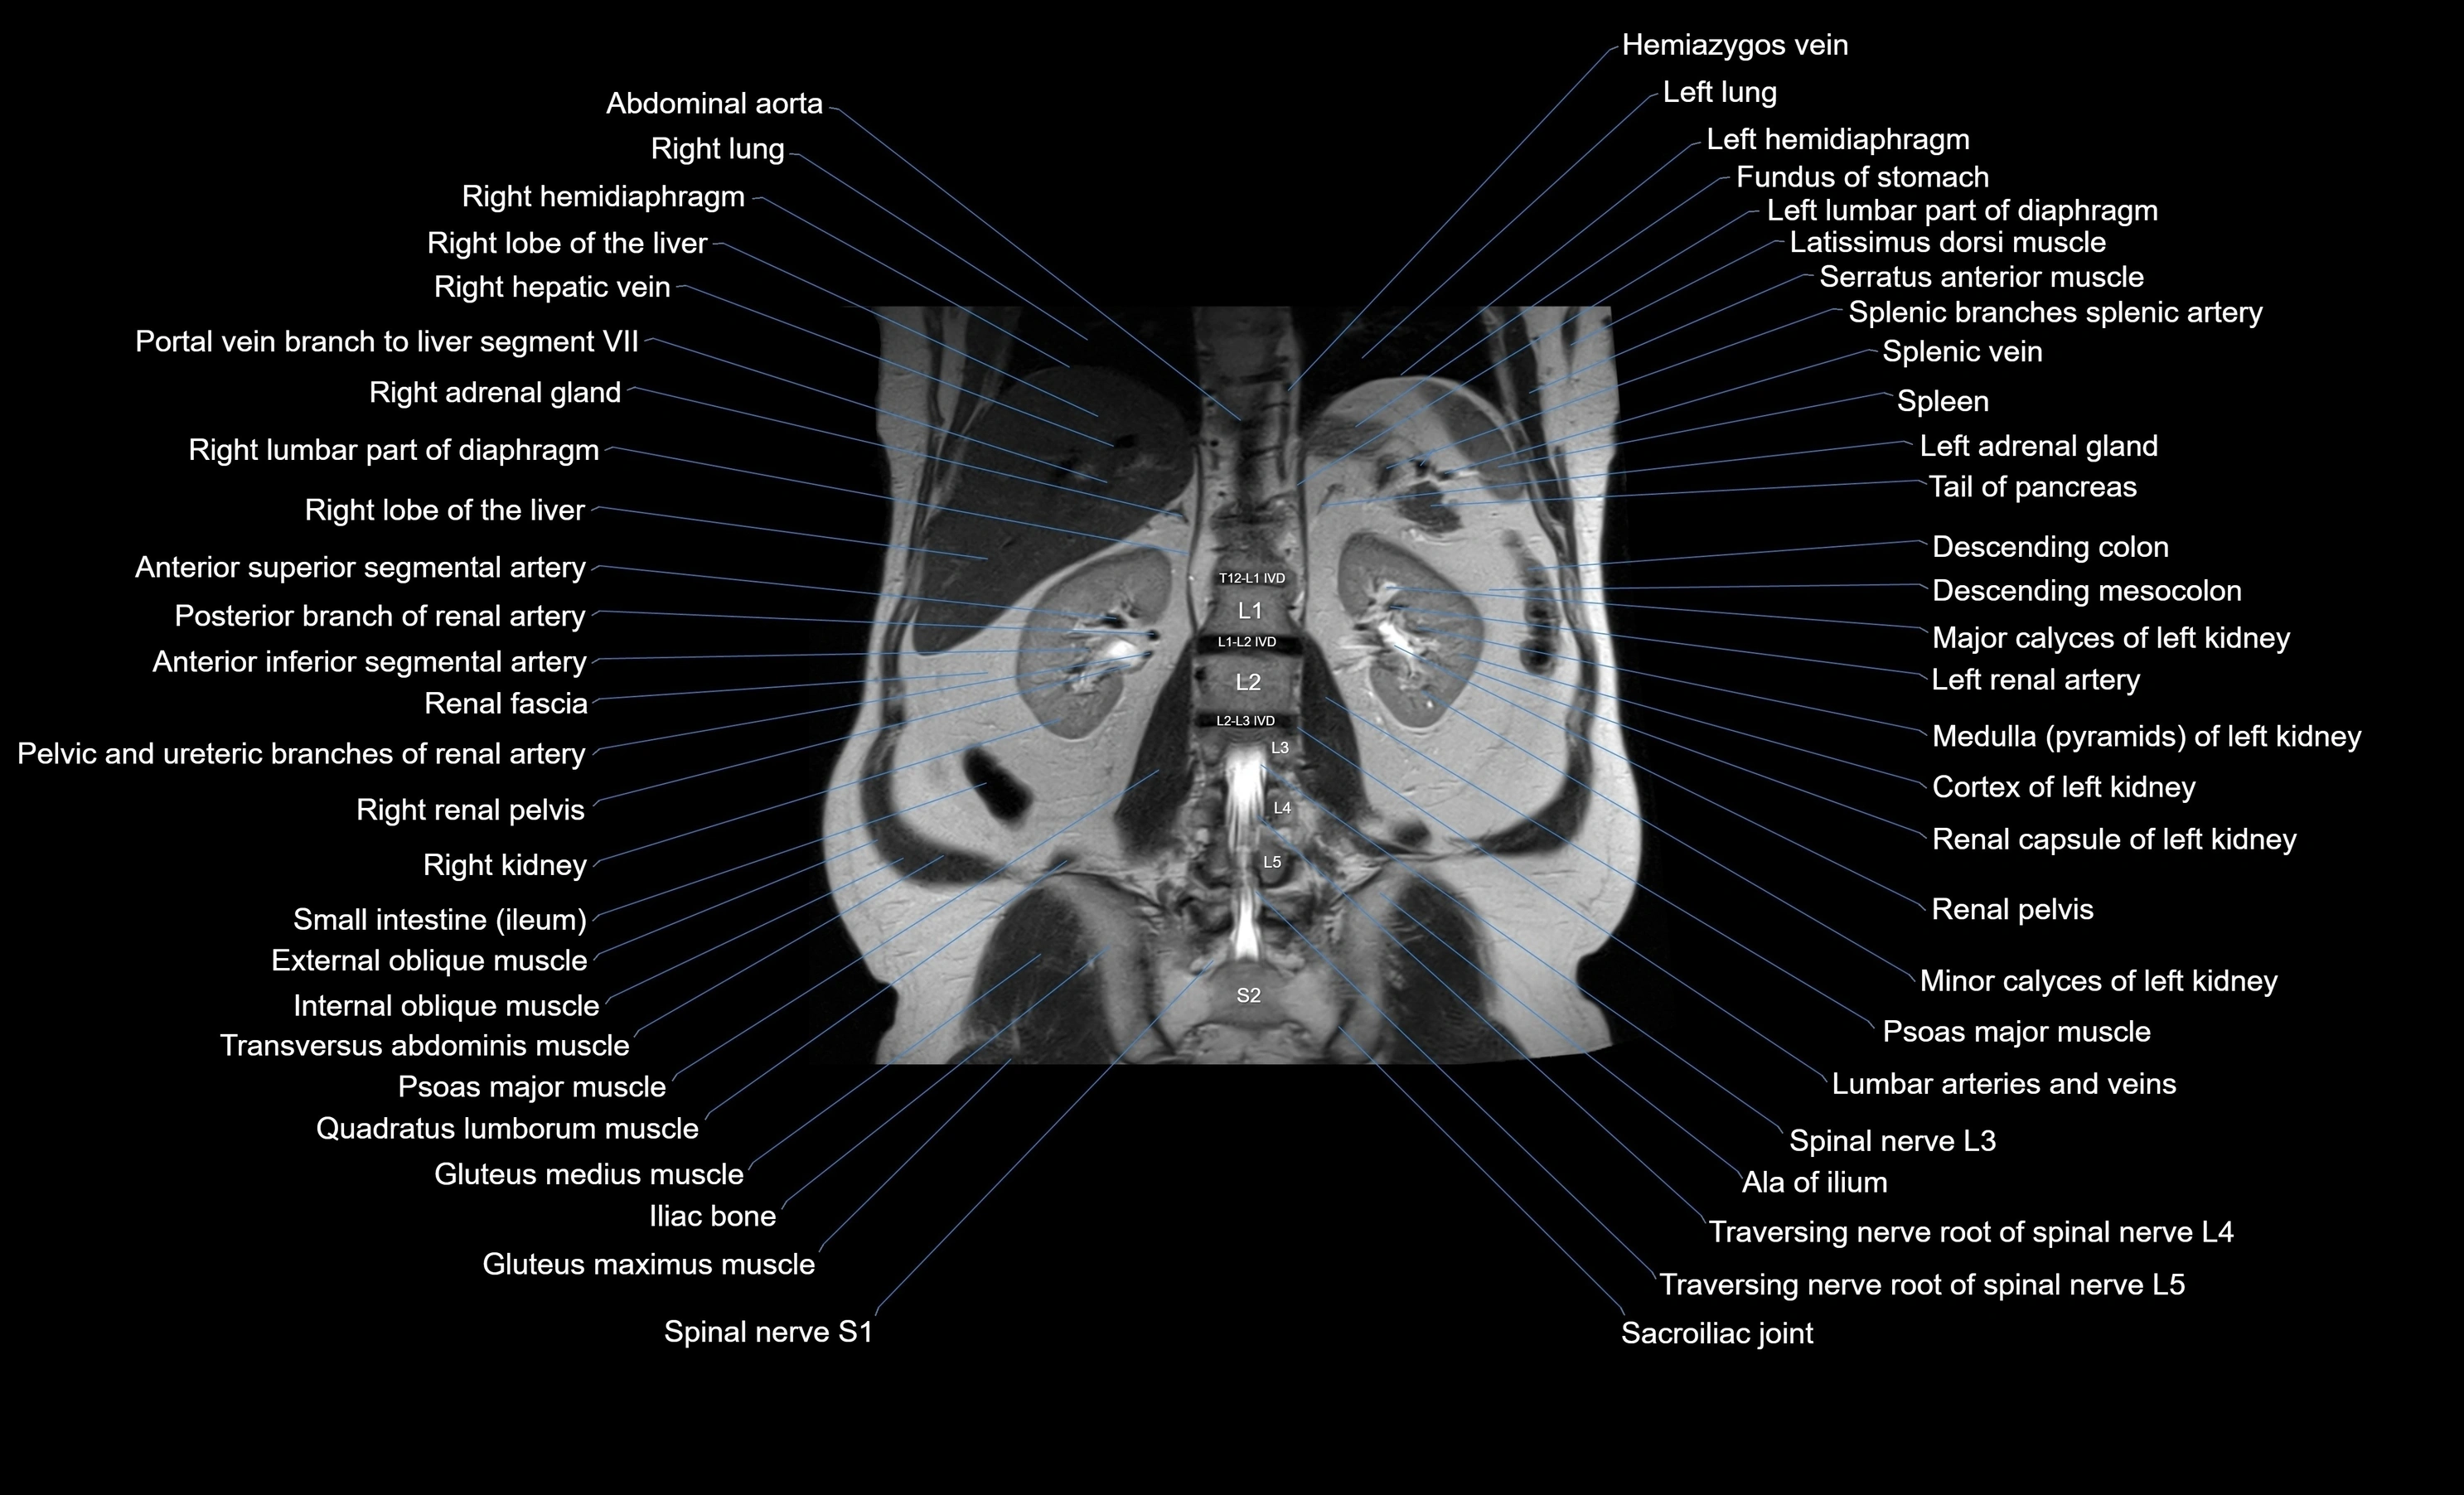

MRI images